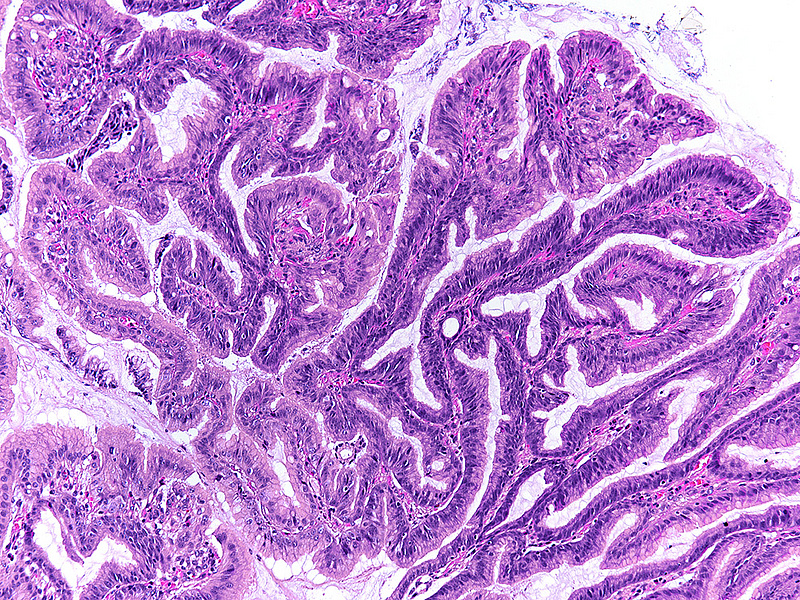

Upon histology, the three polyps showed a similar morphology. The polyps demonstrated irregularly shaped, branching, papillary projections with well-vascularized stroma (Panels A-C). On higher magnification, these projections were lined by dysplastic columnar cells, with hyperchromatic, enlarged and stratified nuclei and a distinctive apical mucin cap, prompting diagnosis of foveolar-type gastric adenoma with low-grade dysplasia (Panels D-F). The background tissue showed non-atrophic oxyntic mucosa, without gastritis, Helicobacter pylori infection or intestinal metaplasia. In summary, the histology was consistent with the newly described variant of foveolar-type adenoma with a raspberry-like appearance.